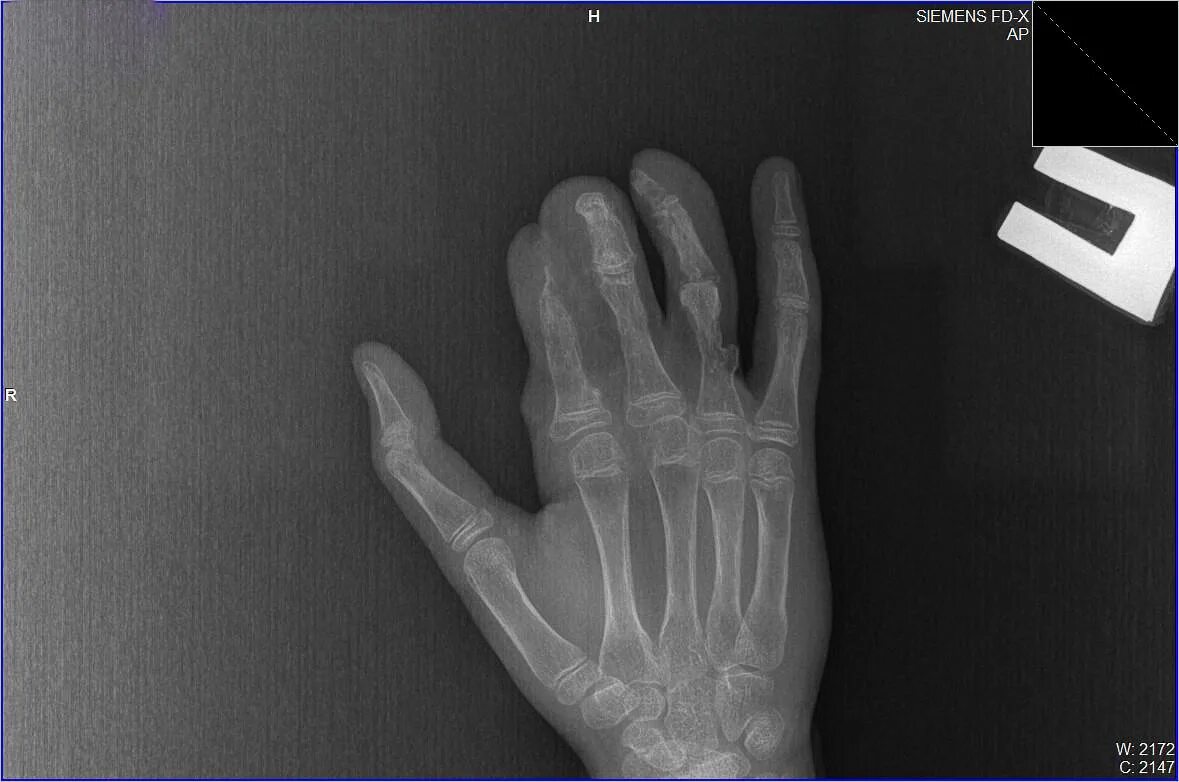

Рука 13 летнего